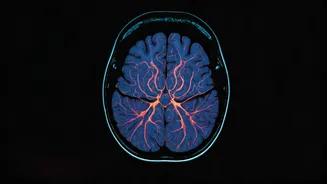

Cognitive changes encompass a variety of symptoms that can affect mental processes and functioning. Brain tumors can disrupt cognitive abilities, leading to memory problems, difficulty concentrating, or challenges with thinking and reasoning. These changes may involve issues with language, such as finding the right words or understanding speech. Patients might experience confusion, disorientation, or personality shifts. Such alterations can be subtle initially but worsen over time. These symptoms occur because the tumor puts pressure on or damages brain regions responsible for cognitive functions. Any noticeable changes in cognitive abilities, particularly when accompanied by other neurological symptoms, necessitate a prompt consultation with a healthcare professional to identify the cause and receive appropriate treatment.

Vision changes can also signal the presence of a brain tumor. Tumors can exert pressure on the optic nerve or affect the visual cortex, causing a range of vision problems. These may include blurred vision, double vision, or loss of peripheral vision. Some individuals experience visual disturbances like seeing flashing lights or floaters. In some instances, the changes in vision occur gradually, while in others, they may appear suddenly. It's important to recognize that vision changes linked to brain tumors are often progressive. Anyone experiencing persistent or unusual changes in vision should seek immediate medical attention. Regular eye exams can help detect early signs of cardiovascular issues, but changes in vision not explained by other issues can indicate problems within the brain.